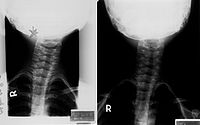

2、X线检查,有利于鉴别不同原因造成的斜颈,如枕颈部畸形所致的骨性斜颈和自发性寰椎旋转性半脱位引起的斜颈一般不会产生胸锁乳突肌的挛缩和肿块,后者多有轻微外伤上呼吸道感染病史。

(1)先天性骨性斜颈 本症多系先天性枕颈部畸形所致,包括短颈畸形、颅底凹陷、半椎体畸形、寰枕融合及齿状突发育畸形。上述疾病可造成斜颈及面部不对称,但一般不会产生胸锁乳突肌的典型条索状挛缩带及肿块,X线检查可明确上述诊断。

(3)自发性寰枢椎旋转性半脱位 寰枢椎旋转性半脱位同样可以引起斜颈,但此病多有轻微外伤或上呼吸道感染病史,主要表现为颈部旋转运动受限及颈部疼痛症状明显,胸锁乳突肌仙无紧张条索带,X线检查可鉴别。